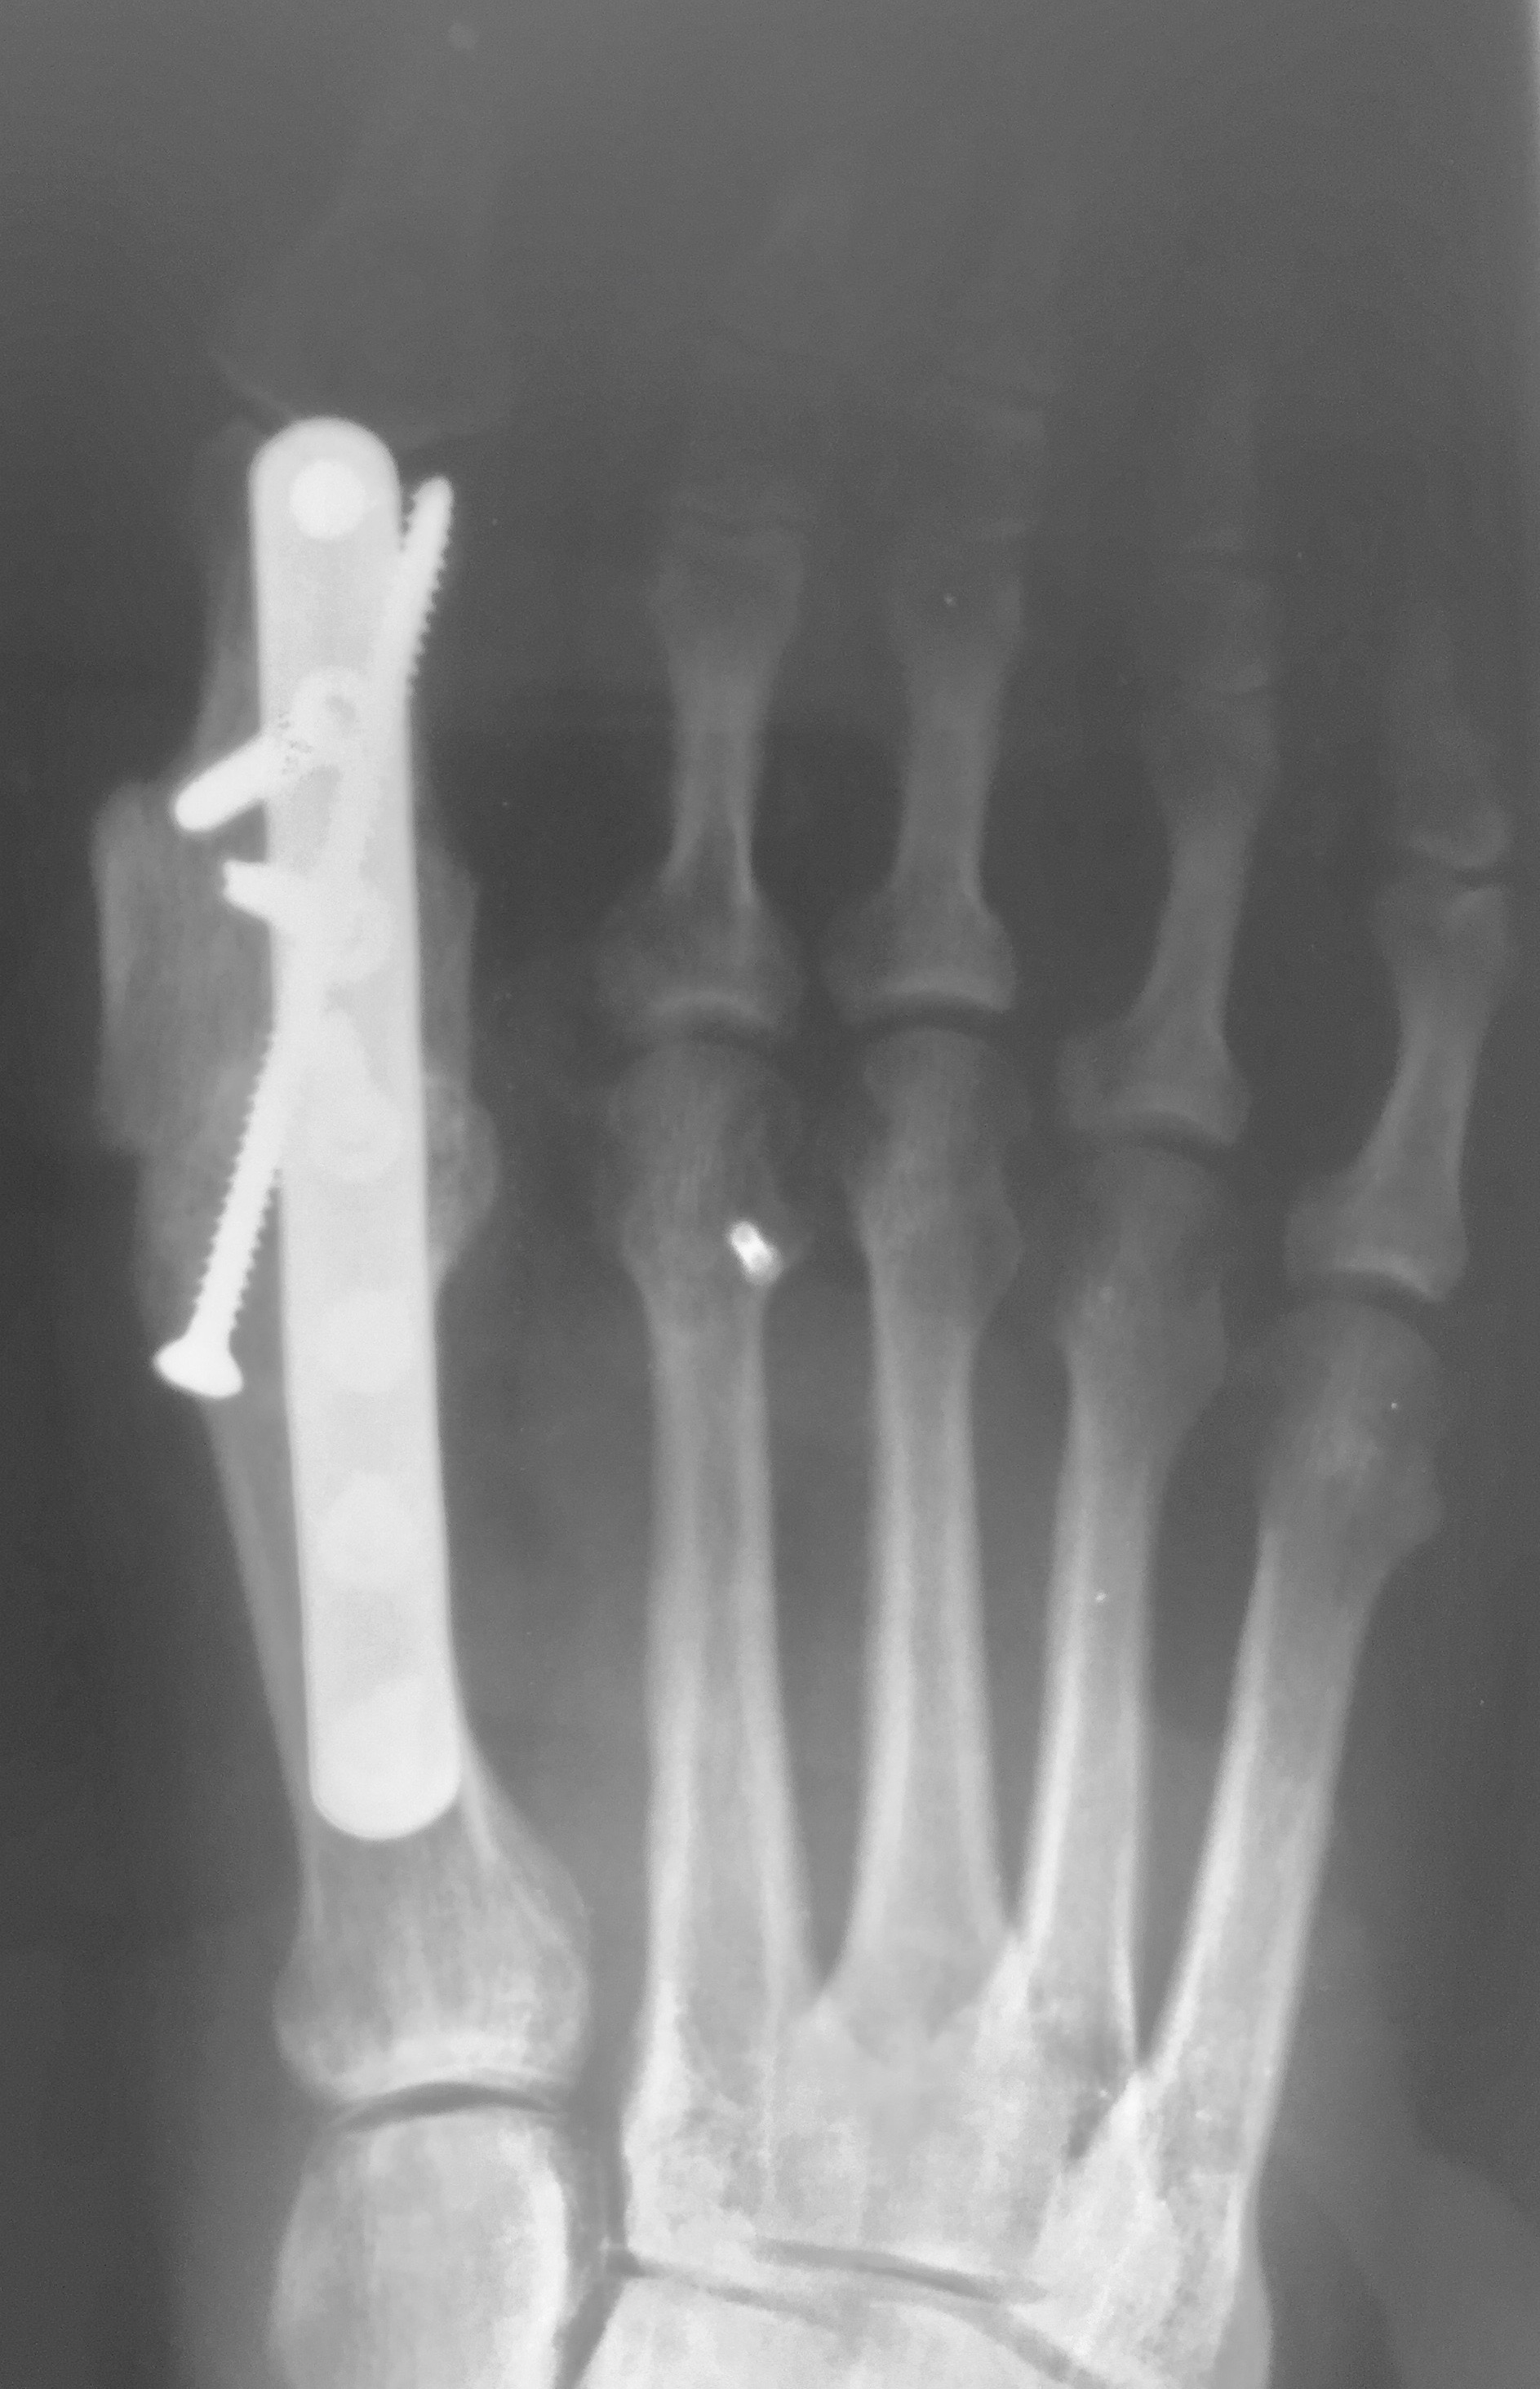

The same principles apply to the foot and ankle. Autogenous bone grafting may be beneficial in many situations including replacing bony defects as well as aiding in deformity correction. Use of autogenous graft allows the foot and ankle surgeon to perform a “positional arthrodesis,” allowing reduction of the deformity with anatomic alignment followed by shear-strain bone grafting across the arthrodesis/fracture site. This enables surgeons to obtain optimal surgical correction while providing the proper environment for stimulation of bony healing. Autogenous grafting for foot and ankle surgery often has limited morbidity as it is within or near the surgical site itself. It is also cost-effective and avoids risks of disease transmission.

When it comes to harvest of autogenous bone from the posterior tuberosity of the calcaneus, surgeons most commonly utilize this harvest location for procedures in the midfoot and the forefoot.5 The calcaneus is a superior source of bone graft in terms of minimizing surgical time due to its close proximity to the primary surgical site. Calcaneal bone graft is a particularly useful compliment to arthrodesis procedures and fracture repair within the forefoot and the midfoot.

Biddinger and colleagues report that one can harvest up to three, eight mm trephine cores with minimal complication risk.16 DiDomenico and coworkers reported harvest of three to five cm3 of bone from the calcaneus using corticotomy and curettage while adding only two to three minutes of surgical time.17 The risk of sural nerve damage is low with the experienced surgeon but one should take care to avoid irritation in this area.15 Disadvantages of calcaneal bone graft include fracture risk, insufficient quality of bone and postoperative incisional irritation from footwear.18 If the calcaneus is unable to provide a sufficient volume of bone graft, a more proximal site of harvest may be necessary.5 Cross and DiDomenico characterize the calcaneus as a safe harvest site.19

We often utilize autogenous grafting for “positional arthrodesis” procedures. A positional arthrodesis allows for optimal positioning and fixation while often leaving a gap or defect due to translating an abnormal or malaligned position to a more anatomic or aligned position. Often the optimal position does not allow for 100 percent bony contact without the risk of shortening or malposition, thus leaving the surgeon with a bony deficit. One may backfill these defects with autogenous bone graft and maintain adequate positioning. However, we recommend as much bony contact as possible while also obtaining optimal position and maximal stability.